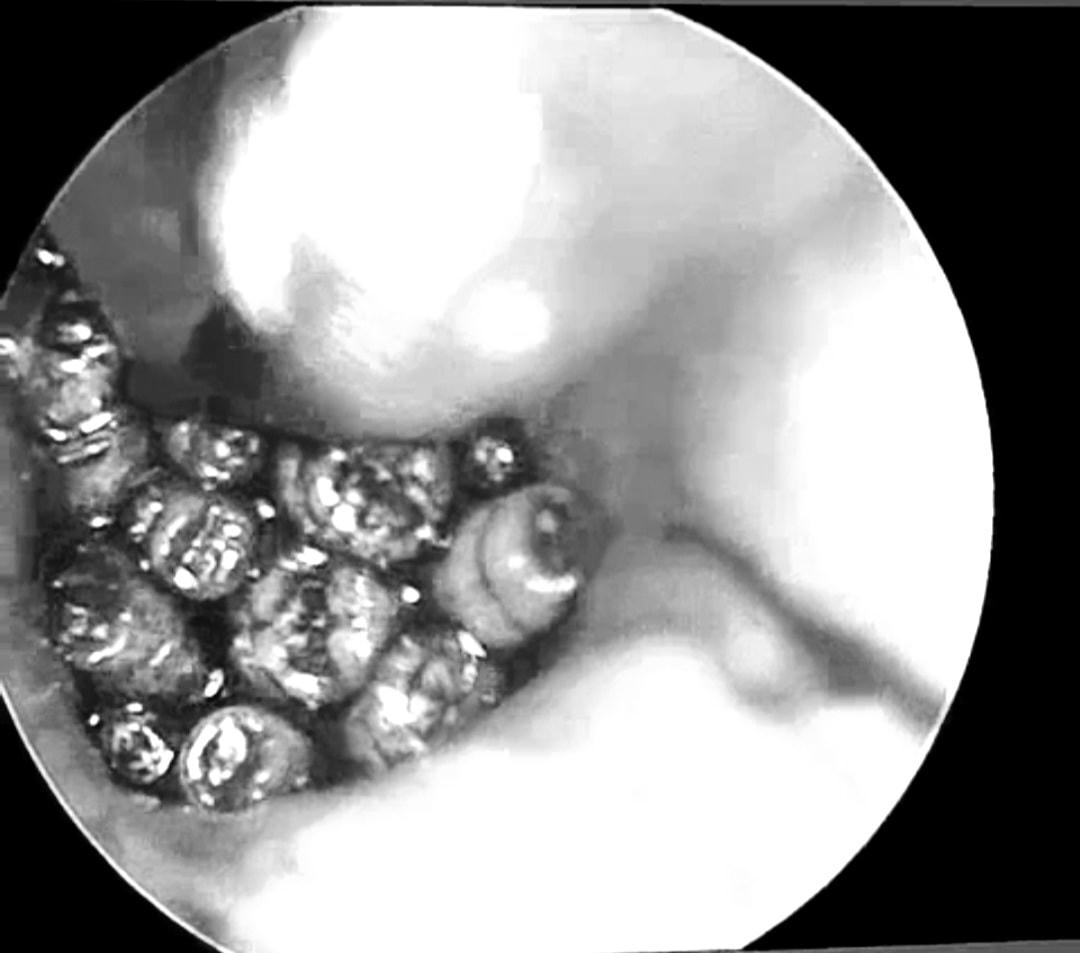

Tiến hành nội soi, các bác sĩ phát hiện ống tai của bệnh nhân Đ.H. hẹp, đọng nhiều máu tươi. Khi hút sạch máu, quan sát thấy dị vật màu trắng di động, nhiều hình ảnh giống con giòi lấp đầy hòm nhĩ, màng nhĩ thủng rộng.

Sau khi làm các xét nghiệm tiền phẫu, bệnh nhân được đưa vào khoa Phẫu thuật Gây mê hồi sức. Tại đây, các bác sĩ khoa Tai Mũi Họng tiến hành nội soi, gắp hàng chục con giòi sống trong tai giữa của bệnh nhân.